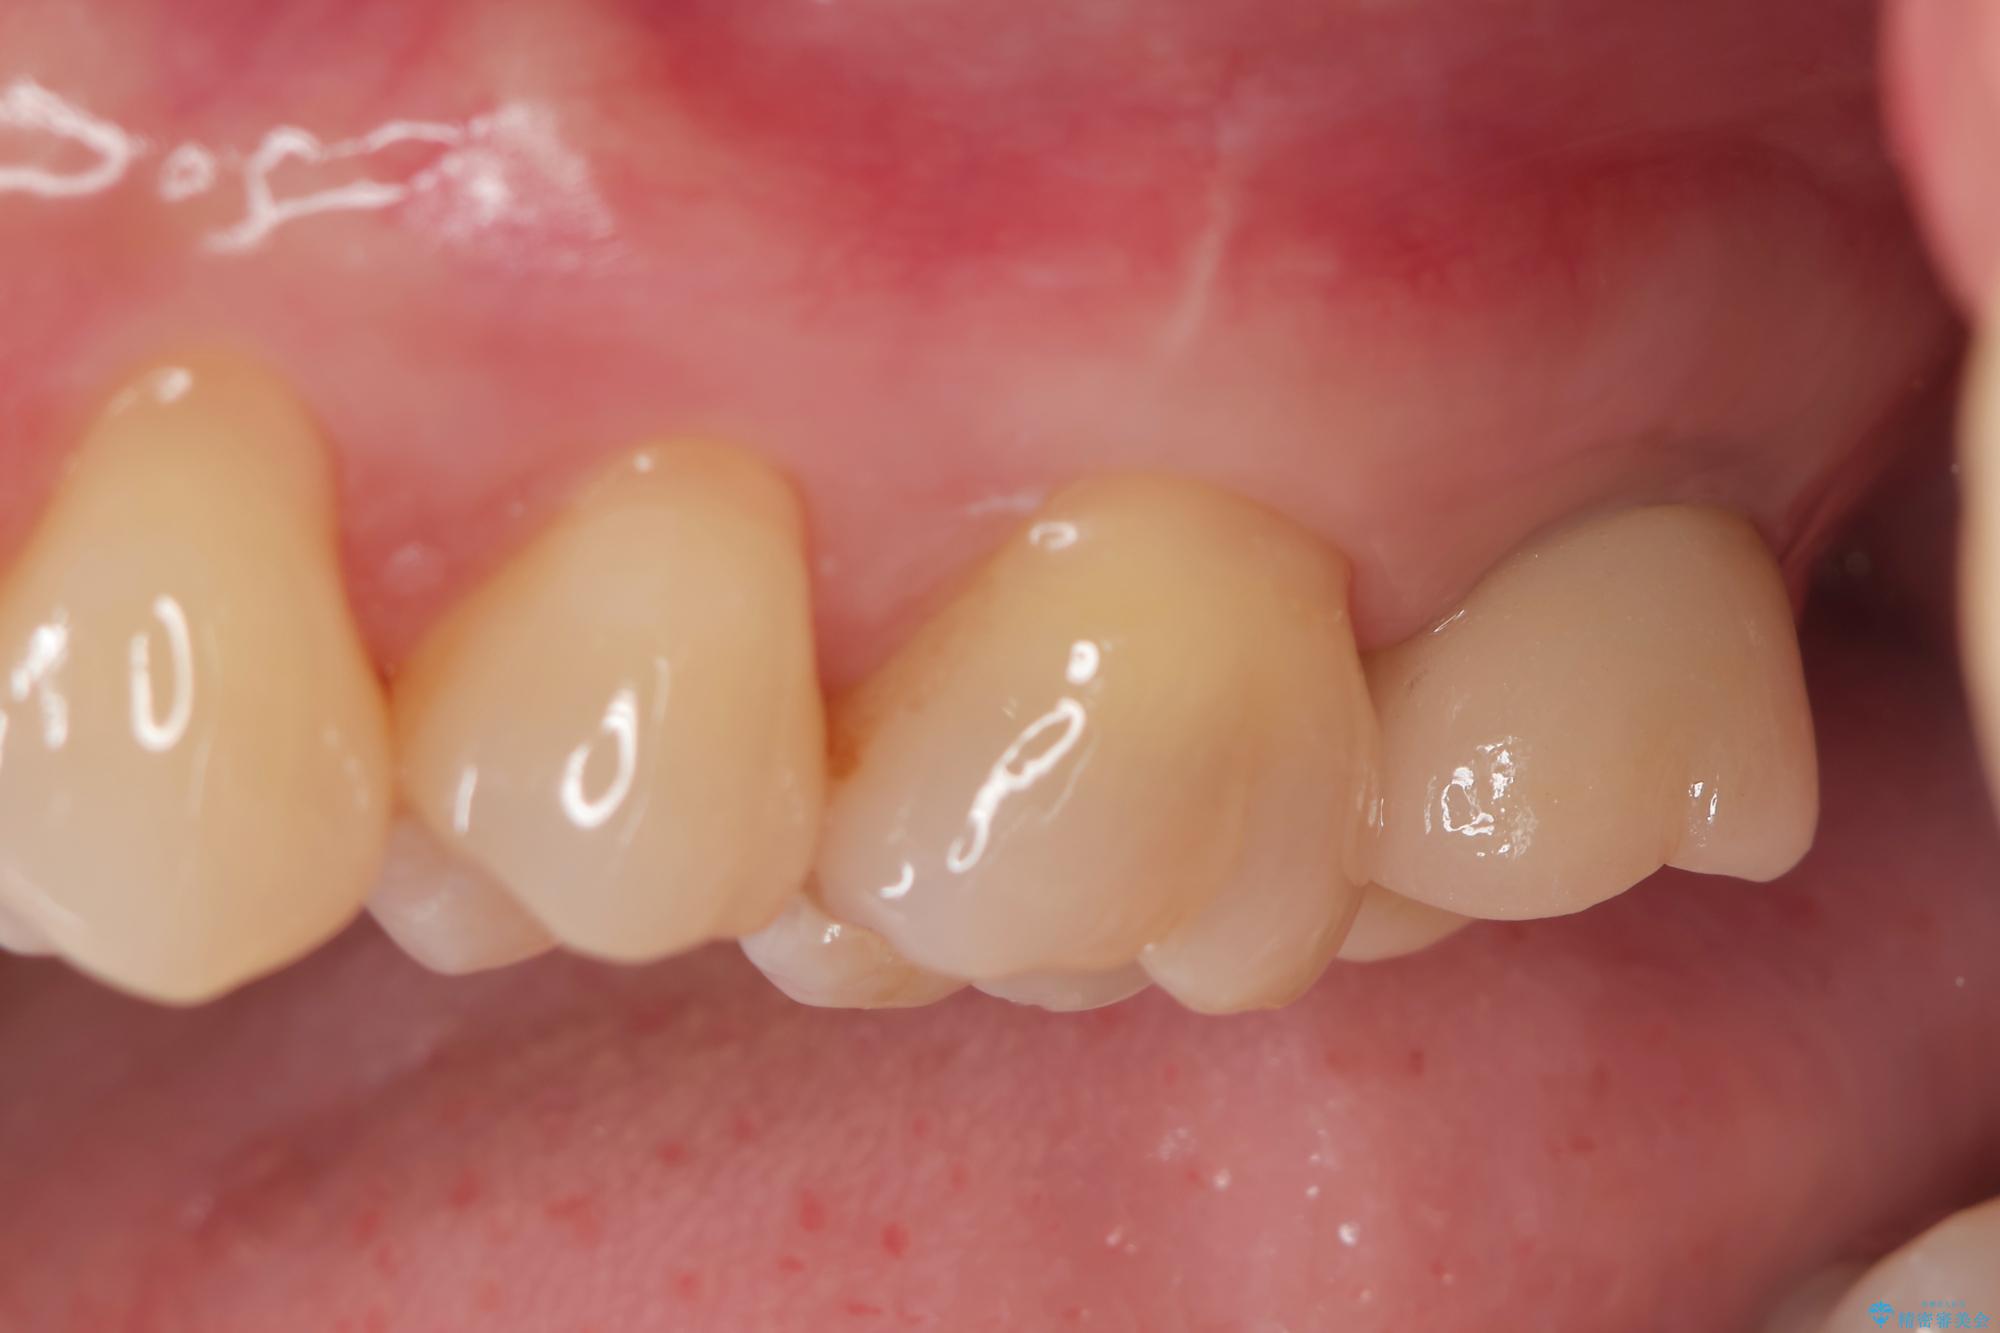

治療を終えて

歯の破折で抜歯を余儀なくされ、ショックが大きかったですが、しっかりとインプラントで咬合機能が回復することができ、喜んでいただくことができました。

治療後

【噛むと歯が疼く】歯牙破折からのインプラント治療 治療後画像 【噛むと歯が疼く】歯牙破折からのインプラント治療 治療後画像 【噛むと歯が疼く】歯牙破折からのインプラント治療 治療後画像 【噛むと歯が疼く】歯牙破折からのインプラント治療 治療後画像